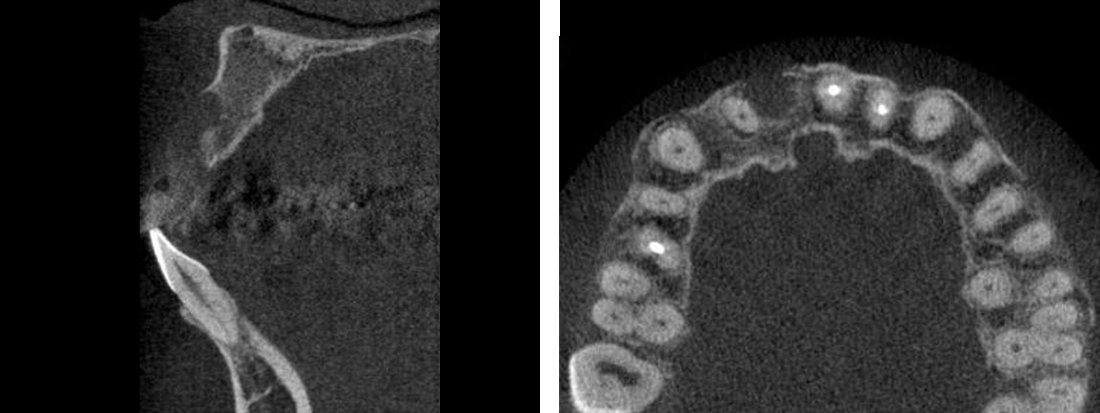

2.インプラントを埋め込む

CT事前にシュミレーション

シュミレーション通りにインプラント埋入

局部麻酔のもと、顎の骨にチタン製のインプラントを挿入します。 このインプラントが 新しい歯の土台となります。